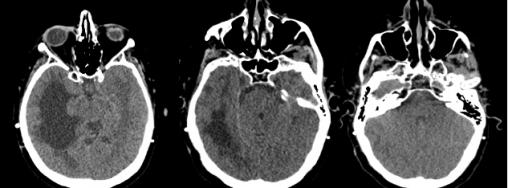

Hydrocéphalie non communicante

Dilatation ventriculaire.